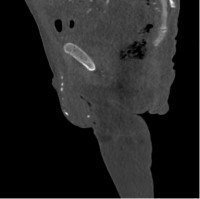

CTA with bilateral runoff was obtained, given the patient’s history of peripheral vascular disease and infected extremity ulcer. The imaging noted severe diffuse generalized arterial vascular calcification throughout all visualized arterial vascular structures including the aorta as well as the large, medium and small arteries (Images 2a and 2b). As noted, the degree/extent of arterial vascular calcifications was severe, essentially involving all arterial vascular structures diffusely.

Images 2a and 2b. Penile and testicular calcifications seen in sagittal view of computed tomography of the abdomen/pelvis